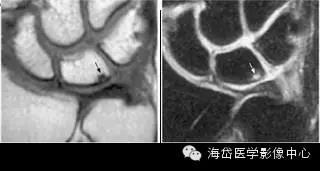

②MRI:MRI对骨髓变化敏感,在骨损伤早期就能反映出骨髓水肿性改变,可做到早期诊断。

随压迫时间延长MRI可见高信号(T2WI)逐渐增强,并形成透镜样改变,晚期形成“双线”或“双环”征。“双环”征提示坏死区内可能有新骨形成,“双线”征表明骨坏死区有瘢痕组织形成。

由于尺骨阴性、阳性变异引起的骨坏死是可逆的,当尺骨变异被纠正后骨坏死可以转化为正常骨结构。因此MRI除可用于早期诊断外还可作为有效的动态观察手段,当骨髓水肿性变化无减轻、消失,反而逐渐明显时,提示临床应早期解除桥联状态(主要是解除压迫),可有效防止月骨、三角骨坏死的发生或降低其发生率。